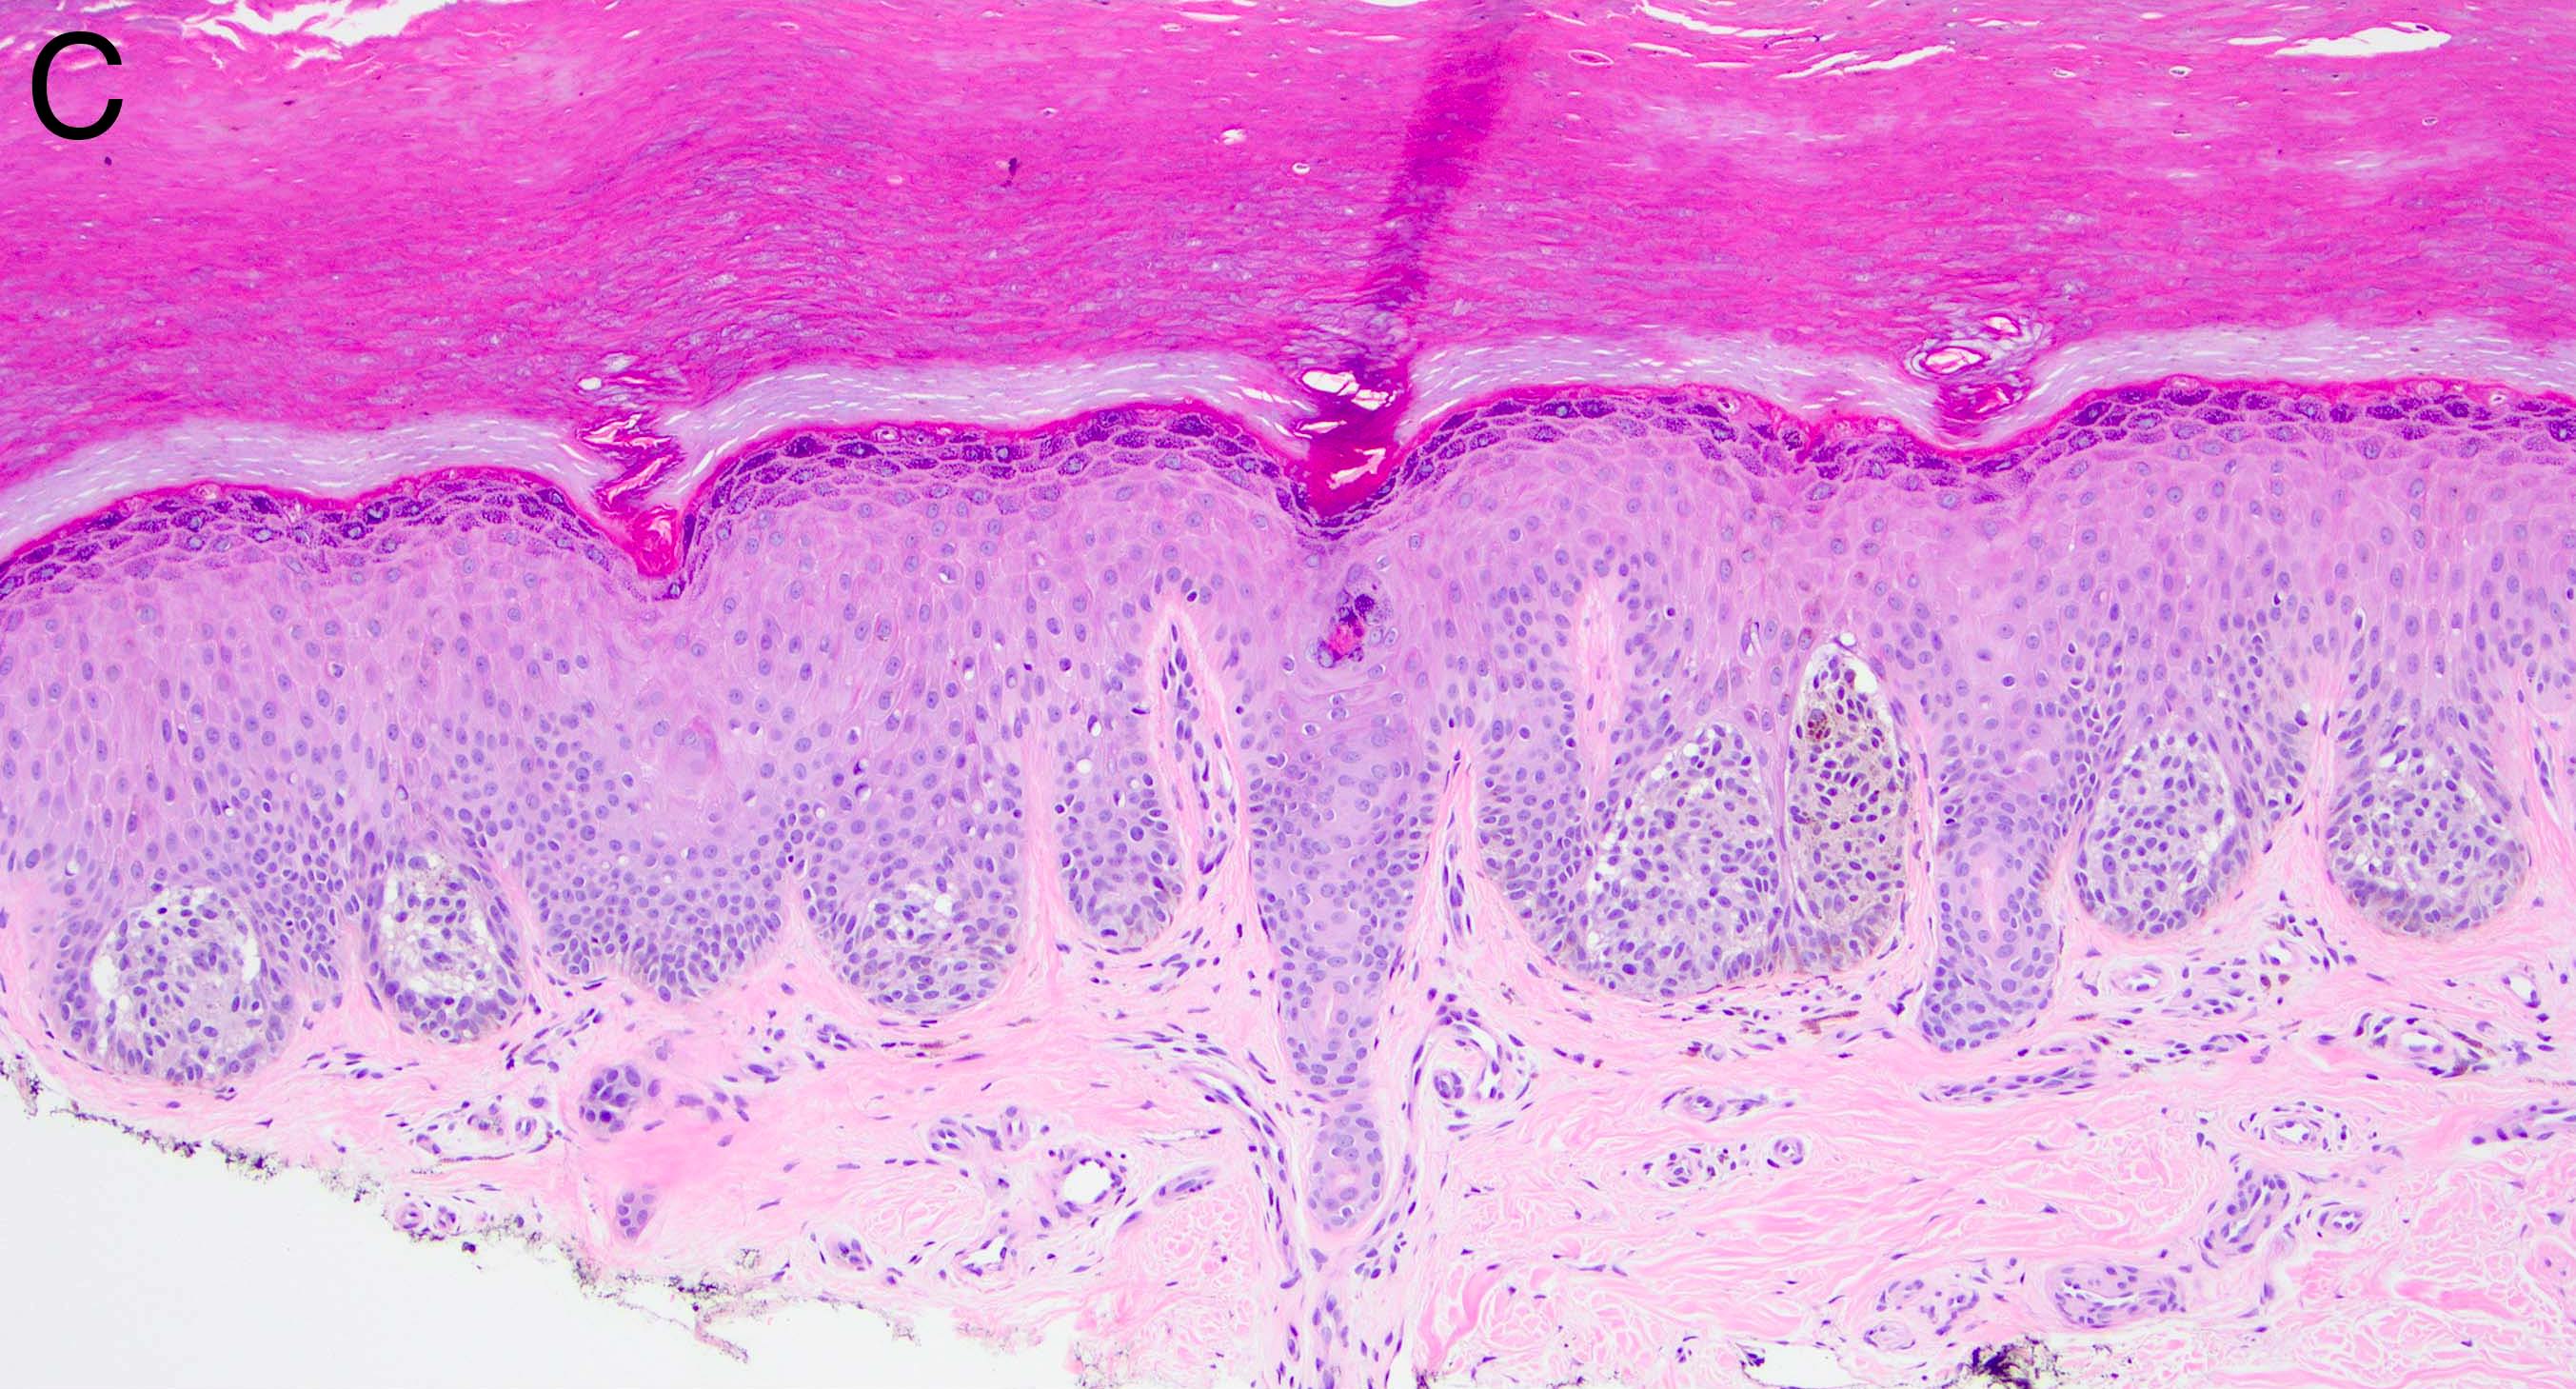

Microscopic (histologic) images

- Melanocytic nevi of the breast (Am J Dermatopathol 2016;38:867):

- May contain large irregular dyshesive nests in close proximity to one another

- Junctional nests may not be centered and can be placed within inter-rete spaces and along sides of rete

- Nests may have variable pigmentation (results in globules seen on dermoscopic exam)

- Nests may have prominent horizontal streaming resulting in rete blunting or epidermal effacement

- Cytologic atypia is common

- Maturation with melanocyte descent should be retained